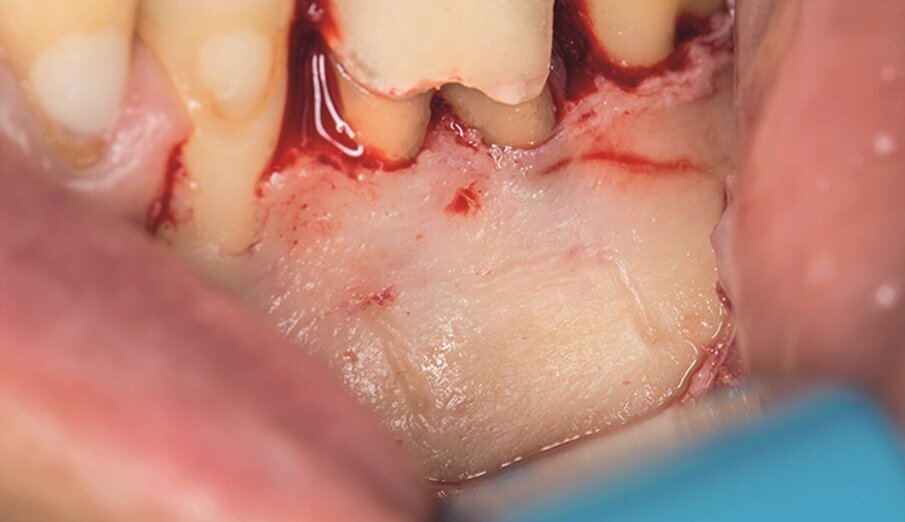

Under local anaesthesia, a full-thickness mucoperiosteal‑ap was reflected, providing visualisation of the buccal bone (Fig. 2g), and the printed template was used to mark the cortical window (Fig. 2h), which was cut with a Piezotome CUBE LED handpiece, and the separated instrument was exposed (Fig. 2i) and removed (Fig. 2j). After apicectomy, retro-preparation was done using ultra sonic tips (ACTEON) and sealed with TotalFill BC RRM Fast Set Putty (FKG) (Fig. 2k). The ‑ap was sutured using 5/0 prolene suture material (Fig. 2l). The sutures were removed 72 hours postoperatively. After two years the patient came to our office for a follow-up radiograph, the tooth was asymptomatic and in function (Fig. 2m).

Fig. 2g: Full-thickness mucoperiosteal flap reflected.